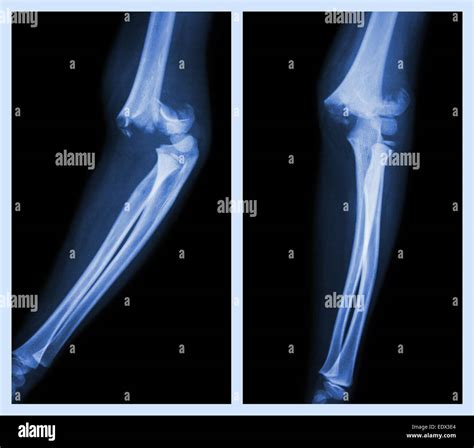

Not all cubitus fractures are the same. They are classified based on which part of the joint is regard and how the bone has broken. Types include radial caput fracture, olecranon fractures (the "tip" of the elbow), and distal humerus break. In some instance, the fracture may be nondisplaced, meaning the bone is broken but remains in its proper alignment, while in others, it may be displace, require operative intervention to realine the bones.

Tomography is the fundament of diagnose a crack in the cubitus. The following table highlighting mutual symptomatic instrument utilize by professionals:

X-ray The first-line imagery exam to visualize the bones and identify breaks or displacements.

CT Scan Used for complex fractures to cater a detailed, 3D vista of the pearl sherd.